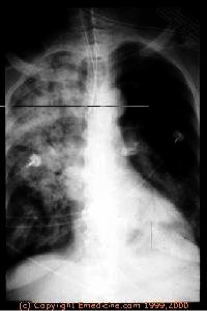

Esophagus Foreign Bodies

- Coins – 75%

- Meat, dentures, disc batteries, etc.

- Common locations: Cricopharyngeus, Aorta/left mainstem bronchus, Gastroesophageal junction

Meat and vegetable matter less common in children – more in adults

Esophageal anomalies found in pts with recurrent impactions

Diagnosis

- Symptoms: Dysphagia, odynophagia, choking & cough

- Physical exam: Drooling, refuses oral intake

- Radiology

- Esophagoscopy

Treatment

- Removal via esophagoscopy

- Disc batteries and sharp objects removal is an emergency due to the risk of perforation

Choking/coughing – aspiration? Sx of resp compromise in 10% due to compression of trachea